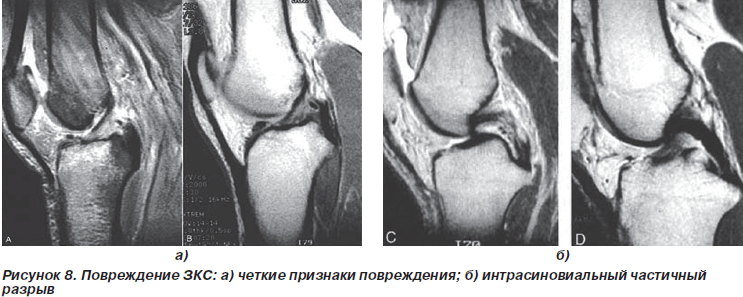

При оценке задней крестообразной связки (ЗКС) МРТ показала отличные результаты. Это, на наш взгляд, связано с тем, что задняя крестообразная связка расположена в складке синовиальной оболочки, поэтому при ее разрыве хорошо видны гематома и инфильтрация мягких тканей, которые ее окружают. При артроскопии также можно оценить состояние ЗКС, однако это требует достаточных навыков и опыта. Это как раз та ситуация, когда оба метода дополняют друг друга.

По нашему опыту, в свежих случаях, когда клинические симптомы не выражены четко, МРТ с последующей артроскопией позволяет сделать правильное заключение о состоянии ЗКС.